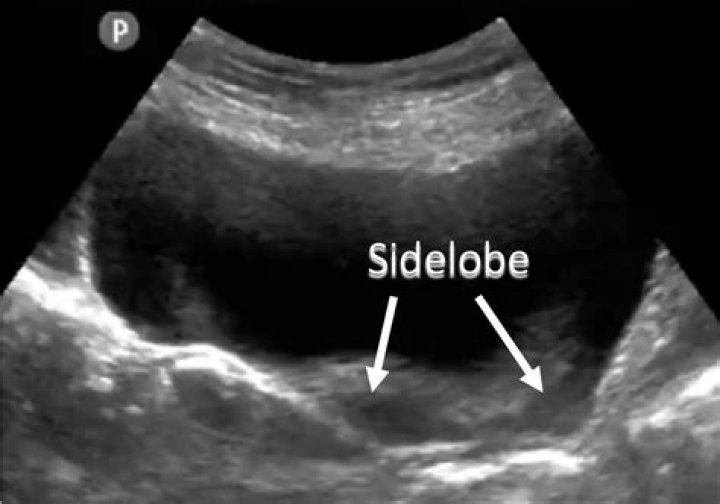

Side lobes and grating lobes artifacts in ultrasound imaging. Side lobes and grating lobes are both unwanted parts of the ultrasound beam emitted off axis that produce image artifacts due to error in positioning the returning echo.

Side lobe artifacts occur where side lobes reflect sound from strong reflector that is outside of the central beam, and where the echoes are displayed as if they originated from within the central beam. These radial beams are called side lobe beams.